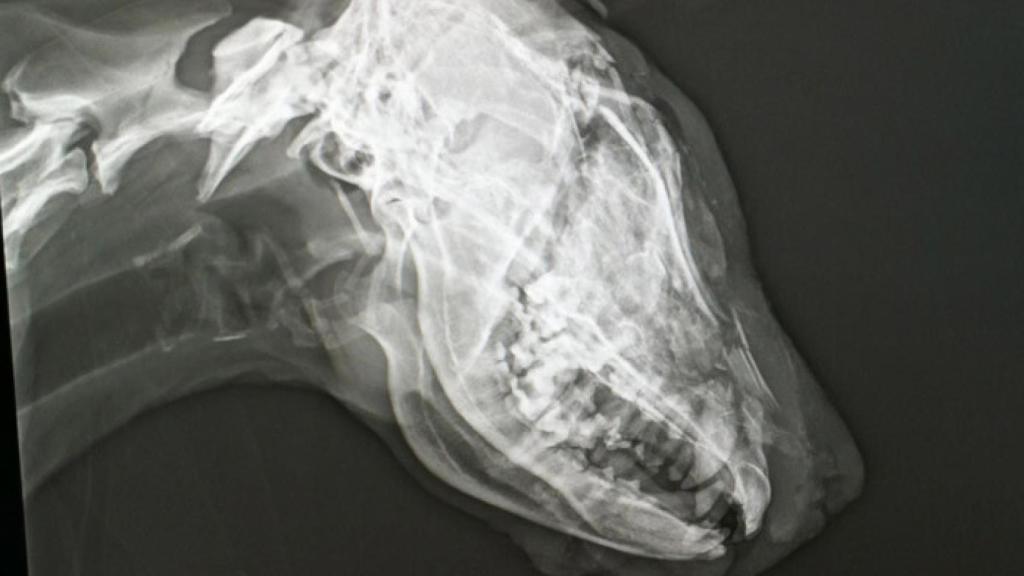

Tras rescatar al animal de la cuneta, las voluntarias de Defensa Animal Zamora llevaron a la perra a urgencias veterinarias, donde "fue imposible" salvarle la vida "dado que le habían partido el cráneo antes de atarla a la bola del vehículo".